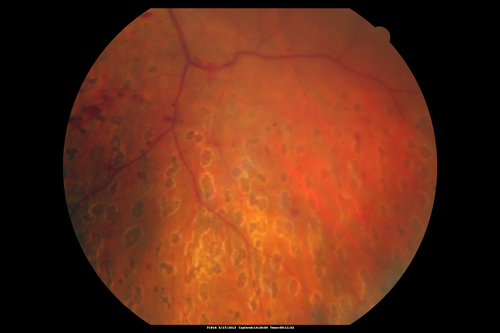

Proliferative Diabetic Retinopathy - Fresh and Old Scatter (Panretinal) Photocoagulation (Laser) - Neovascularization is regressing

1 month after initial laser